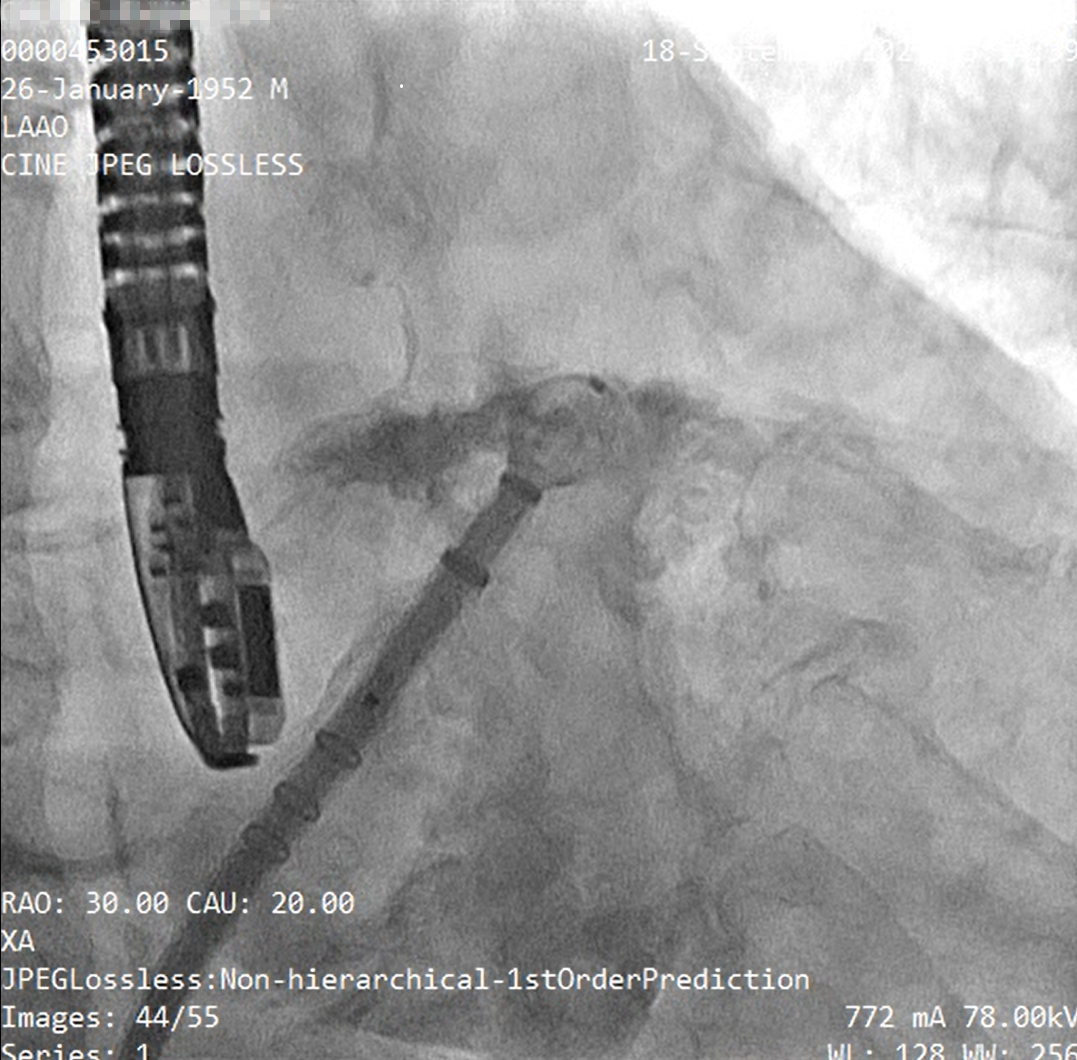

释放左心耳封堵器呈〝FLX BALL〞

经造影及食道超声检查后释放WATCHMAN FLX左心耳封堵器